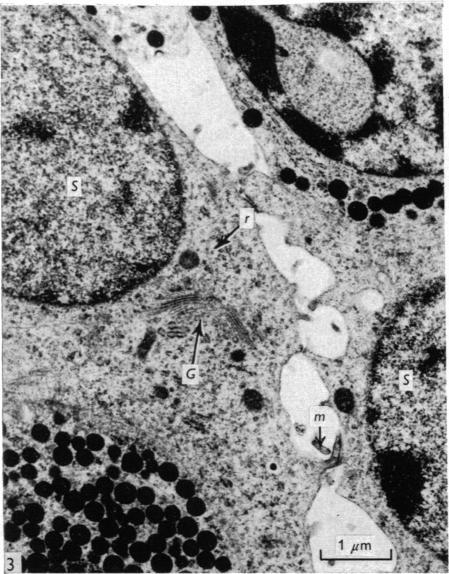

Some observations on the ultrastructure of the stellate cells of the pars distalis of the guinea-pig.

The ultrastructural appearance of the stellate cells of the guinea-pig adenohypophysis is described, and their functional significance discussed.